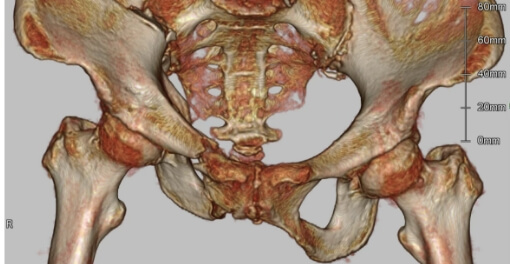

寛骨臼骨折症例

粉砕の強い右寛骨臼骨折の症例。前方・後方アプローチによる観血的整復固定術を行いました。